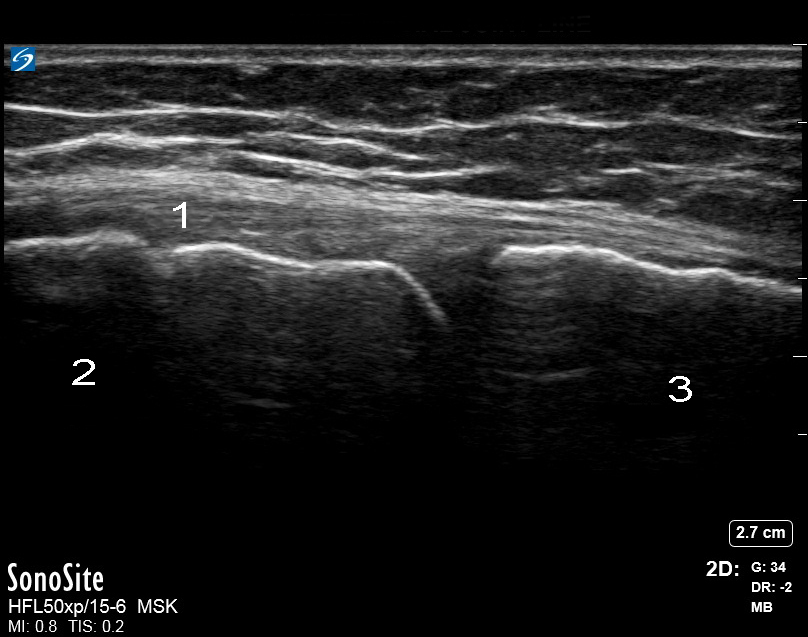

Bild: Knie, Ligamentum collaterale mediale (LCM)

1. Ligamentum collaterale mediale (LCM)

2. Femur

3. Tibia